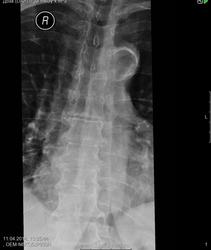

Правосторонний сколиоз до 10 градусов. Снижена высота передних краев позвонков ThVI, ThVII, с признаками клиновидной деформации. Локальное усиление кифоза на уровне ThVI - ThVII. Боковые остеофиты ThX-XI, ThXI-ThXII.

Заключение: Рг картина дегенеративного спондилеза, правостороннего сколиоза 1 ст, компрессионный перелом ThVI, ThVII?

Это клиновидность как признак дегенеративных изменений. За переломы сомнительно.

Остеохондроз грудного отдела, III период, остеопороз тел позвонков. Костно-травматических изменений не выявлено.